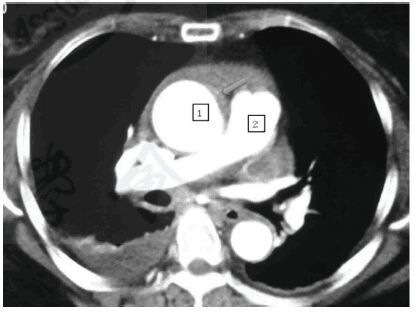

患者,女,50岁,既往有高血压病史8年,口服硝苯地平控释片降压治疗,平时未监测血压,以“突发胸闷、意识丧失1 d”收入本院。患者入院前1天患者小便后突发胸闷、憋气,伴腰部酸痛,继而意识丧失,约3~4 min后自行恢复意识,至当地医院就诊,HR 140 次/min,血压测不出,TNI 1.9 ng/mL,WBC 15×109/L,胸部CT示中大量心包积液、右侧胸腔积液,未见主动脉夹层及肺栓塞征象(图 1)。予多巴胺、多巴酚丁胺后血压可维持。次日转至本院急诊,入院后查体:BP 122/88 mmHg(1 mmHg=0.133 kPa),HR 120 次/min,律齐,未闻及瓣膜杂音,双侧桡动脉、股动脉、足背动脉搏动对称。辅助检查:ECG示窦性心动过速,无ST-T改变。UCG示LV 38 mm,EF57%,中量心包积液。实验室检查:WBC 17.54×109/L,TNI 0.816 ng/mL,D-二聚体 15.95 μg/mL。根据患者的临床症状和检查结果,需鉴别诊断主动脉夹层、肺栓塞、急性冠脉综合征(ACS)、急性心肌心包炎等疾病。外院CT检查结果已排除前两种疾病可能,而非ST段抬高心肌梗死较少出现心包积液,故ACS暂不支持,拟择期行冠脉造影检查进一步排除。患者补诉半月前有上呼吸道感染病史,白细胞、CRP等炎症指标升高,不排除急性心肌心包炎可能,故给予抗感染、营养心肌、多巴胺升压、利尿等药物治疗。患者入院后胸闷症状有所缓解,将多巴胺逐渐减停。但入院第6天,患者突发剧烈胸痛、背痛,伴腰痛、大汗,查体:BP 108/85 mmHg,HR 99次/min,律齐,未及瓣膜杂音,双侧桡动脉、股动脉、足背动脉搏动对称。ECG示Ⅱ、Ⅲ、AVF导联ST段抬高0.1 mV。因考虑不排除主动脉夹层累及冠状动脉开口的可能,遂首先复查主动脉CT,结果明确为Ⅰ型主动脉夹层(图 2)。次日行升主动脉置换术+全主动脉人工血管置换术+支架象鼻术,术中显示,血性心包积液,升主动脉壁呈紫色并有渗血。术后患者病情平稳,好转出院。而此时再次仔细观察患者第一份胸部CT隐约可见升主动脉壁有新月形增厚(图 1箭头所示),考虑为主动脉壁内血肿可能性大。

图 1 患者发病时第1份胸部CT

仔细回顾患者第一份胸部CT时,可发现升主动脉段似有新月形主动脉壁内血肿征象。主动脉壁内血肿占AAS的5%~30%,同主动脉夹层一样,也分为A型(累及升主动脉)和B型,A型主动脉壁内血肿发生在心包内主动脉段时可导致主动脉壁渗血而出现心包积液,发生在心包外主动脉段时可出现胸腔积液。A型主动脉壁内血肿的院内病死率与A型主动脉夹层相似,30%~40%的A型壁内血肿会进展为急性主动脉夹层,且症状发作的前8 d风险最高。2014ESC指南中指出,对于合并心包积液、主动脉周血肿或大动脉瘤的A型主动脉壁内血肿,应行急诊外科手术治疗,而绝大多数的A型主动脉壁内血肿均需要24 h内进行紧急手术。